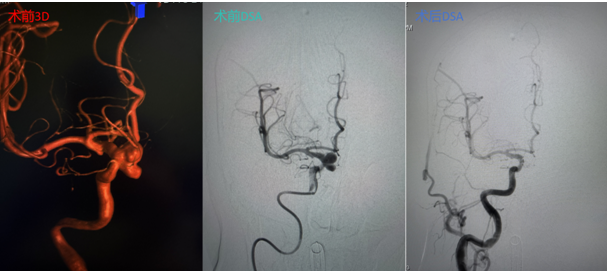

术后即刻造影显示,动脉瘤腔内血流消失,载瘤动脉通畅无阻,手术取得圆满成功,患者已康复出院。